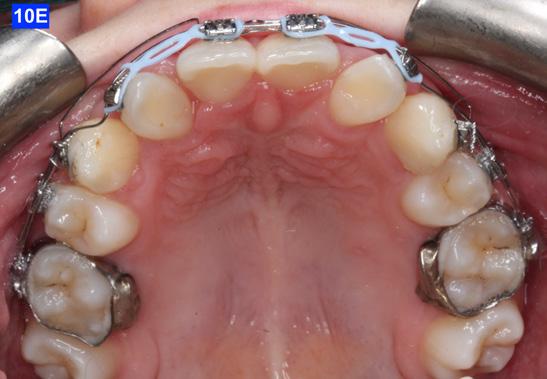

placed between the maxillary central incisors and the cuspids, on a .018 ss arch wire.8 The purpose of this center bend is to move the roots apart. A side effect of this center bend is that the crowns have a tendency to move together. Therefore, an OCS was placed between the maxillary central incisors and the cuspids. (Figure 10 – A, B)

After the maxillary cuspids were in contact with the second bicuspids, we had to ascertain that there was adequate width in the inter-radicular space. A center bend - “V” pointing gingivally was

To protract the maxillary lateral incisors into the arch, the bite was opened using composite build-ups on the mandibular first molars. The protraction was started with a .012 ligature tie, and the resiliency of the arch wire created the labial movement of the lateral incisors (Figure 10 - C).

Figure 8A: TADs in situ, frontal view 8B: TAD in situ, right lateral view 8C: TAD in situ, left lateral view 8D: Power arms Figure 9A: Maxilla, occlusal view 9B: Maxilla, occlusal view 9C: Maxilla, occlusal view Figure 9D: After the removal of the Hyrax, occlusal view Figure 10A: Center bend “V” pointing gingivally Figure 10B: OCS between the cuspids and the central incisors Figure 10C: Composite build-ups on the mandibular first molars Figure 10D: Adrian “U” bend spring

The final labial movement and de-rotation was done by the combined use of an Adrian “U” bend spring and an EC (a .016 SS and a .014 NiTi) (10 – D, E, F). When the maxillary lateral incisors settled in their proper site, the leveling of the maxillary arch was initiated. The progression of the arch wires was a .016 NiTi, a .0.18 NiTi, a .018 SS and the final arch wire, a .019 x .025 SS. There was only a .018 SS arch wire in the mandible. The remaining spaces were closed with a combination of the OCS, EC, and triangular elastics (1/4” – 4.5 oz) (Figure 11-A).